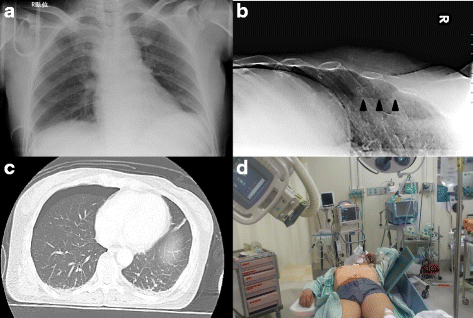

Backgraound: An occult pneumothorax is a pneumothorax that is not seen on a supine chest X-ray but is detected by computed tomography scanning. However, critical patients are difficult to transport to the computed tomography suite. We previously reported a method to detect occult pneumothorax using oblique chest radiography (OXR). Several authors have also reported that ultrasonography is an effective technique for detecting occult pneumothorax. The aim of this study was to evaluate the usefulness of OXR in the diagnosis of the occult pneumothorax and to compare OXR with ultrasonography.

Methods: All consecutive blunt chest trauma patients with clinically suspected pneumothorax on arrival at the emergency department were prospectively included at our tertiary-care center. The patients underwent OXR and ultrasonography, and underwent computed tomography scans as the gold standard. Occult pneumothorax size on computed tomography was classified as minuscule, anterior, or anterolateral.

Results: One hundred and fifty-nine patients were enrolled. Of the 70 occult pneumothoraces found in the 318 thoraces, 19 were minuscule, 32 were anterior, and 19 were anterolateral. The sensitivity and specificity of OXR for detecting occult pneumothorax was 61.4 % and 99.2 %, respectively. The sensitivity and specificity of lung ultrasonography was 62.9 % and 98.8 %, respectively. Among 27 occult pneumothoraces that could not be detected by OXR, 16 were minuscule and 21 could be conservatively managed without thoracostomy.

Conclusion: OXR appears to be as good method as lung ultrasonography in the detection of large occult pneumothorax. In trauma patients who are difficult to transfer to computed tomography scan, OXR may be effective at detecting occult pneumothorax with a risk of progression.